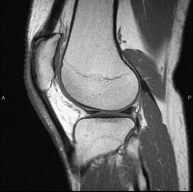

- Knee MRI

Examination to study joint injuries, such as meniscal tears and cruciate ligament tears (only detectable through this test), chondropathy or cartilage wear, and a multitude of other disorders resulting from sports activities and degenerative changes (osteoarthritis). It lasts approximately 18 minutes. It is a radiation-free procedure.

- Knee MRI arthrography

Examination to study injuries to small anatomical structures of the joint, such as cartilage and menisci, mainly following surgery. Prior to the examination, a contrast fluid is injected into the joint, guided by X-ray imaging. The total duration of the two procedures is 50 minutes.